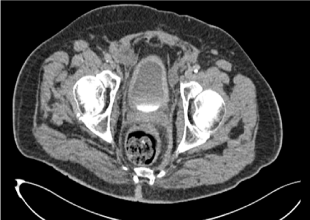

A 66-year-old man was admitted after experiencing painless gross hematuria for a month. The patient’s medical history was significant for diabetes and coronary artery bypass surgery 20years ago. The familial history was unremarkable. The physical exam was normal. Laboratory data were within the normal ranges except for many red blood cells on urinalysis. Pelvis Ultrasound just revealed a thickening of the bladder wall. A CT-scan of abdomen and pelvis showed no obvious bladder mass or distant metastases, but only a diffuse thickening of the bladder wall with bilateral enlargement of the inguinal and iliac lymph nodes (Figure 1). On cystoscopy, multiple small sessile tumors were found in the left bladder wall, base and dome. A transurethral resection was performed. Pathology reports showed a signet ring cell subtype of bladder adenocarcinoma infiltrating the lamina propria and muscular is (stag pT2). We performed a gastroduodenoscopy, colonoscopy and CEA marker level. The normal findings excluded an extravesical primary tumor site. The tumor was then considered to be a primary signet ring cell carcinoma of the bladder. The patient was operated with a radical cystoprostatectomy with an ileal conduit and bilateral pelvic lymphadenectomy. We should mention that a frozen pelvis was found during the surgical operation. Routine pathology examination of the surgical specimen revealed a poorly differentiated adenocarcinoma of the bladder composed of signet ring cells with an abundant mucin pool with invasion of the peri vesical fat (Figure 2). Right ureteral margin was tumor free although left ureteral margin was initially focally reached by tumor. The histopathological staging was pT3bN1M0. Immunohistilogical studies had shown expression of cytokeratin 7, CEA and CA 19-9 but not CD-X2 (Figure 3). The patient was discharged on the 8th day. Postoperative adjuvant chemotherapy with Carboplatin and Gemcitabine combination was started. The patient received six cycles of chemotherapy, but died six months later from a heart attack.

Figure 1 Abdominopelvic computed tomography showing a diffuse thickening of the urinary bladder.

PRSCC has usually a poor prognosis is as it is not diagnosed at an early stage2 where CT does not show obvious bladder mass. To our knowledge, our case is unique by the fact that there are no clear bladder mass or distant metastases shown on the CT scan. Only diffuse thickening of the bladder with inguinal and iliac lymph node enlargement was noted. A reason why more alert and attention should be taken toward such atypical cases in order not to misdiagnose any PSRCC of the urinary bladder. Treatment modalities for primary signet ring cell carcinomas are multiple, and include surgery (transurethral resection of the bladder tumor, radical cystectomy), chemotherapy, and/or radiotherapy. Erdogru et al.,14 showed that radical cystectomy is the best available surgical option for patients. In fact, only one case was reported on cystectomy with orthotopic neobladder for the treatment of primary signet-ring cell carcinoma of bladder.15